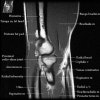

팔꿈치 관절의 MRI 단면 영상

2. Axial section

1) The tendons of the Biceps Brachii and Brachiallis muscles transversely as they insert onto the Radius and Ulna respectively. 2) The distal Triceps tendon is also well evlauated in this plane.